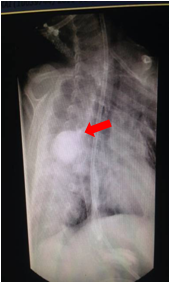

2.颈、胸、腹正侧位X线摄片示导管卷曲或造影显示食道近端盲袋。